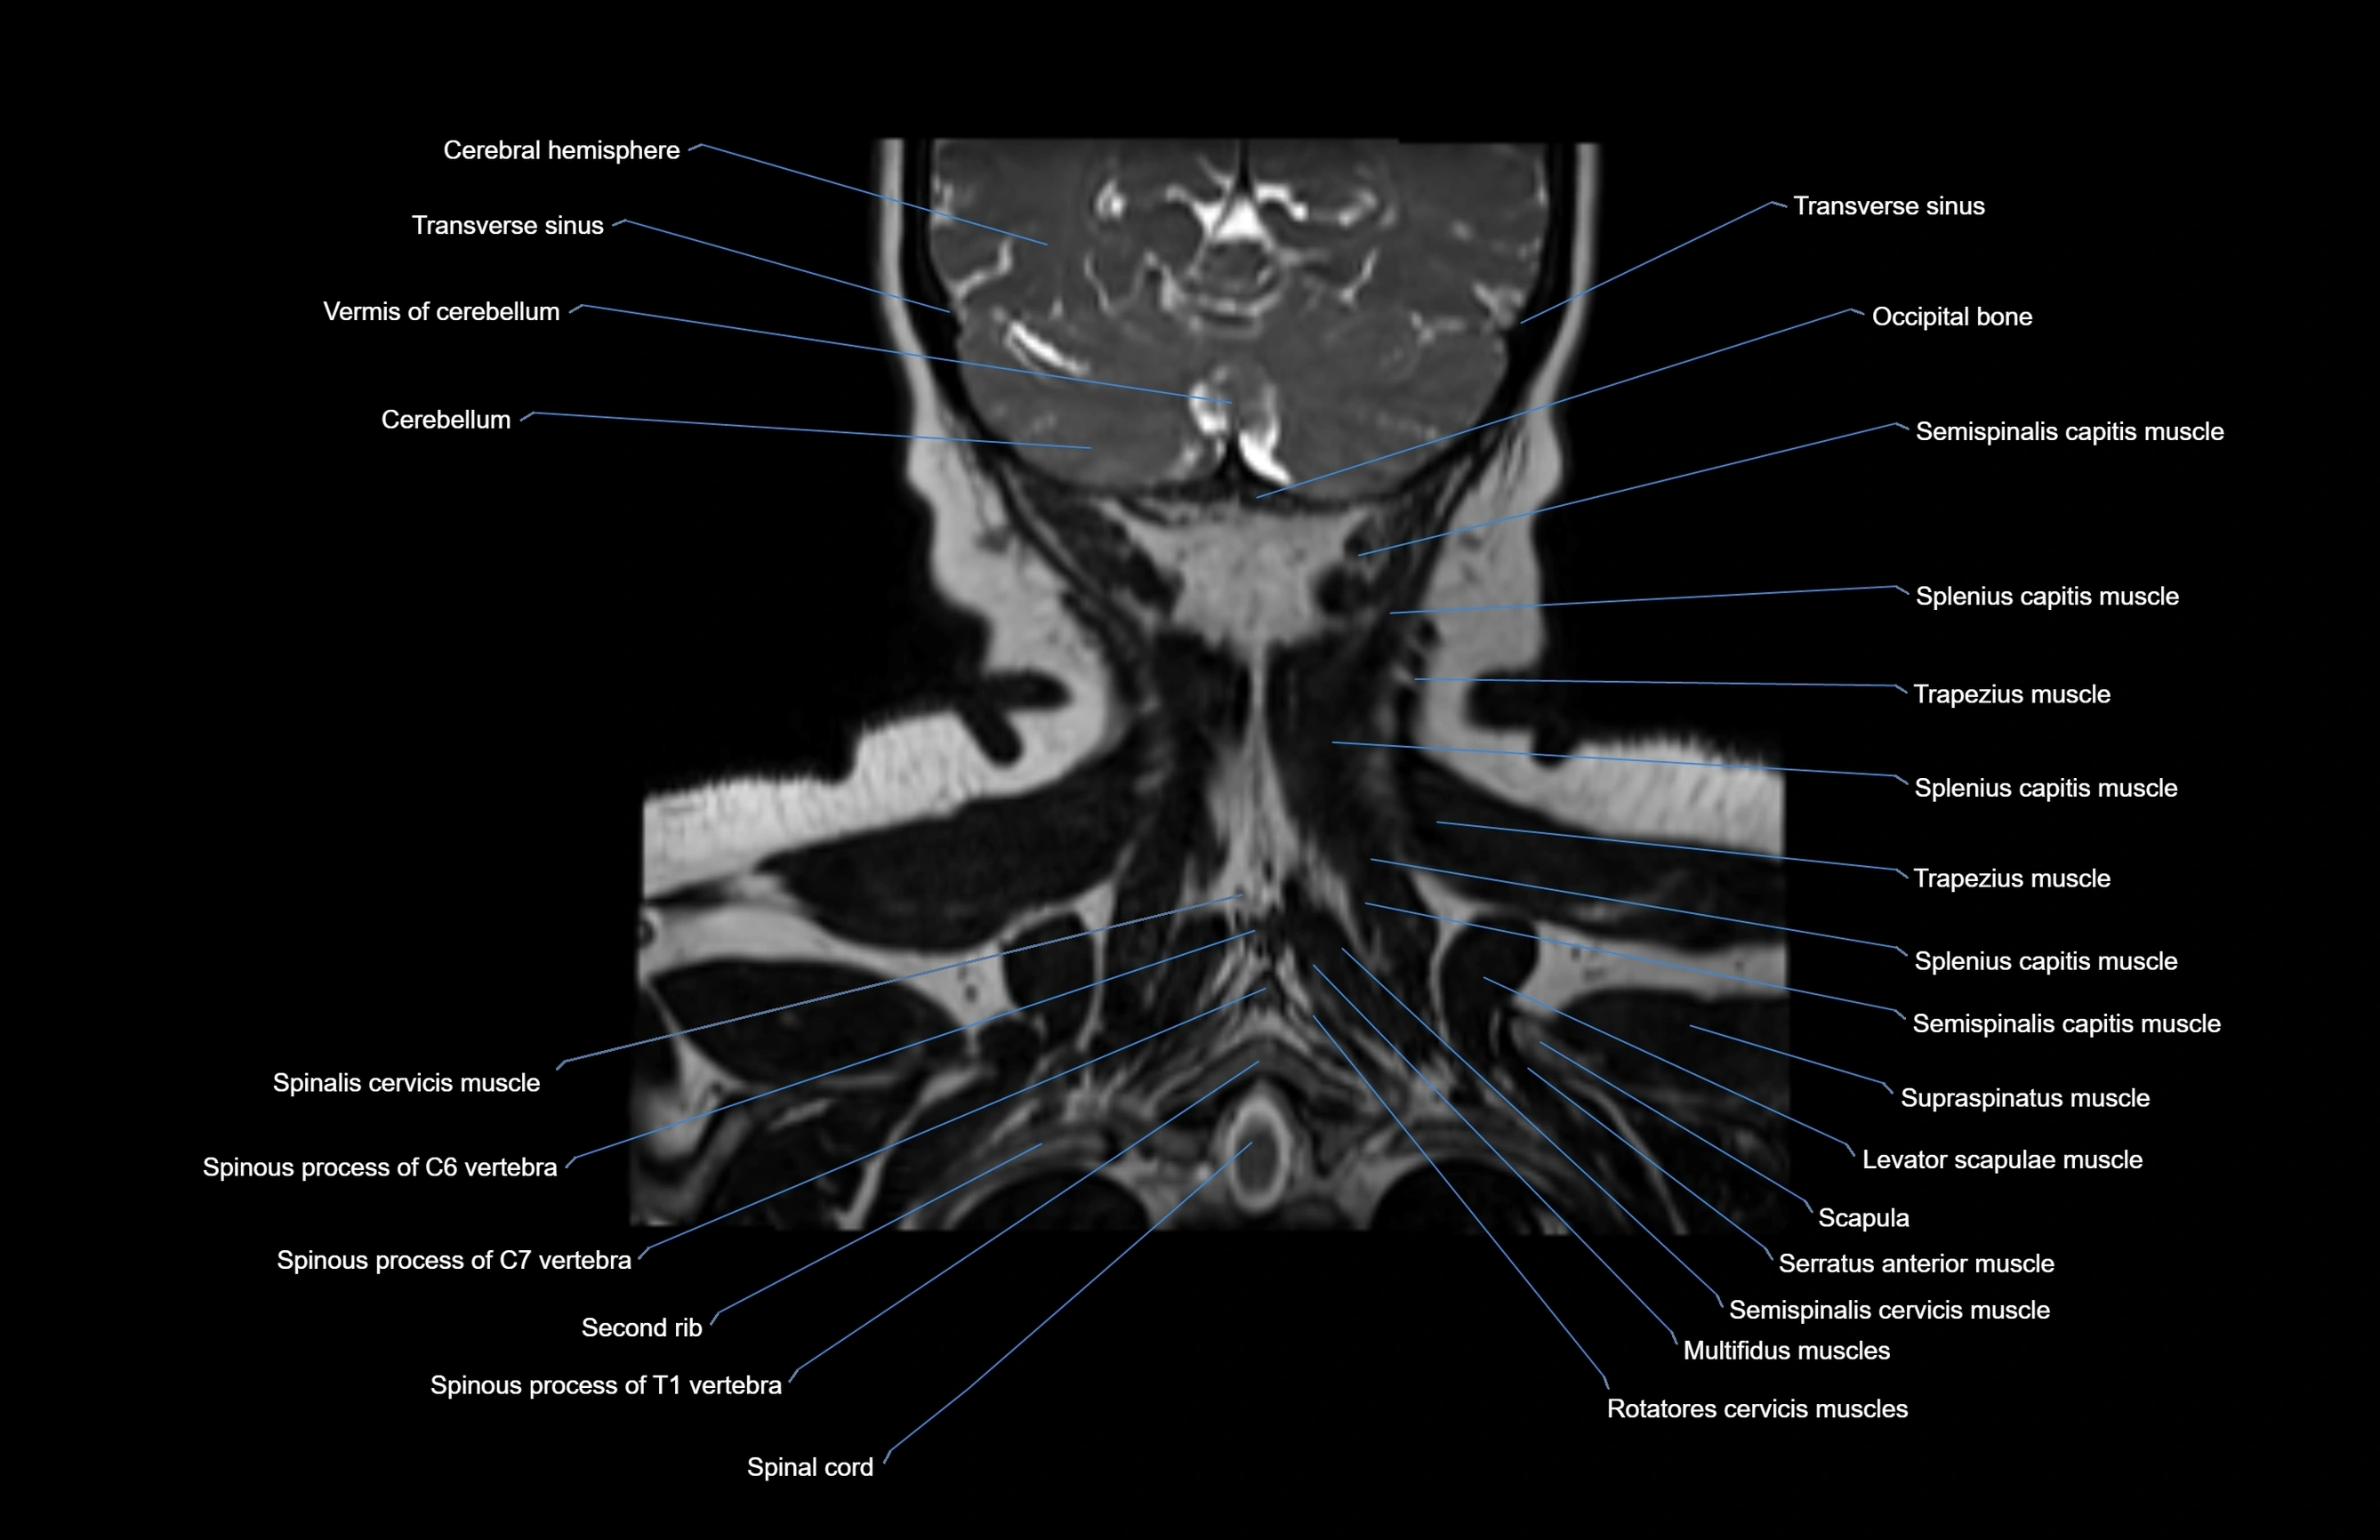

MRI images